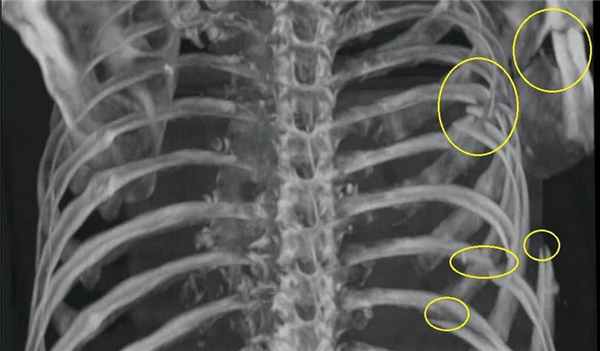

- Рентген грудной клетки. Обычно поставить верный диагноз помогает обзорная рентгенограмма в переднезадней проекции. На снимке хорошо видна локализация переломов и их количество.

Пальпация грудной стенки может выявить наличие нескольких переломов ребер. Некоторые врачи считают, что у здоровых пациентов с незначительной травмой адекватной является клиническая оценка. Тем не менее, для пациентов с клинически значимой тупой травмой обычно проводят рентгенографическое исследование грудной клетки, с целью выявления сопутствующих травм (например, пневмоторакса, ушиба легких Ушиб легкого Ушибом легкого называют посттравматическое кровоизлияние и отек легких без разрыва. (См. также Обзор торакальной травмы (Overview of Thoracic Trauma)). Ушиб легкого является частой и потенциально. Прочитайте дополнительные сведения ). Многие переломы ребер не заметны на рентгенограммах грудной клетки; в этих случаях могут быть проведены специфические исследования визуализации ребер, но идентификация всех случаев переломов ребер с использованием рентгенографии не является необходимой. Выполняют другие тесты, направленные на выявление сочетанных повреждений, заподозренных клинически.